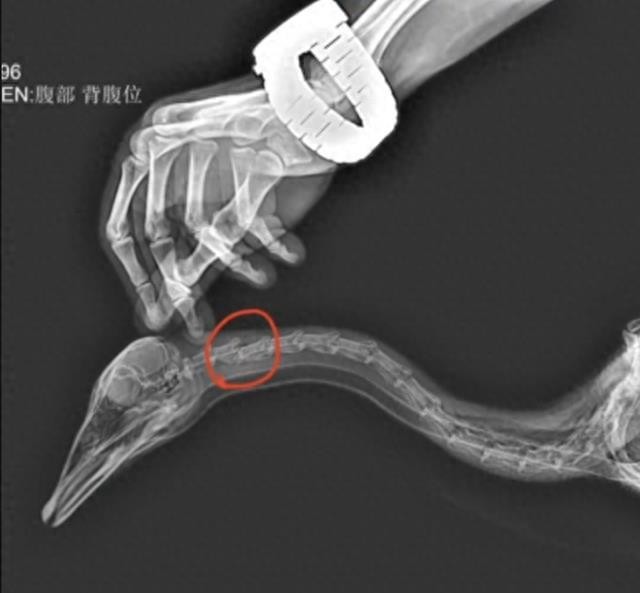

这位游客将大宝的颈椎第二骨节踢到骨折,大宝最终不治身亡,而郭先生和肇事者被警方带走,经过调解,男子向郭先生道歉,官园方也不再追究,而网友们并不买账,这名男子的说法是自己的做法属于紧急避险,也就是说大宝的行为已经威胁到了他们的生命安全,在迫不得已的情况下,不得不做出的紧急措施,这个才叫做紧急避险,而大宝只是对他们一家人进行了驱赶,大宝本身的体型并不大,对人类也十分友好,和游客们能和谐相处,从来不会主动攻击游客,没有给男子造成任何威胁,因此网友认为男子的行为并不属于紧急避险。